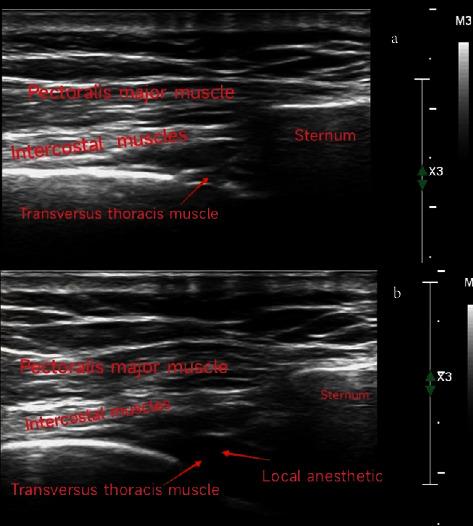

Minimally invasive closure of transthoracic ventricular septal defect (VSD) has been widely used in paediatric patients. This retrospective study aimed to explore the use of transversus thoracis muscle plane block (TTMPB) in the minimally invasive closure of transthoracic VSD in paediatric patients.

In total, 110 patients were included in the final analysis. Perioperative fentanyl consumption of the TTMPB group was not different from that of the non-TTMPB group (5.90 ± 1.32 g/kg vs. 6.25 ± 1.74 g/kg,  = 0.473). Both the time to extubation and postanesthesia care unit (PACU) stay were significantly shorter in the TTMPB group than in the non-TTMPB group (10.94 ± 10.31 min vs. 35.03 ± 23.52 min for extubation, and 42.55 ± 16.83 min vs. 59.98 ± 27.94 min for PACU stay, both  < 0.001). Furthermore, the postoperative paediatric intensive care unit (PICU) stay in the TTMPB group was significantly shorter than in the non-TTMPB group (1.04 ± 0.28 d vs. 1.34 ± 1.05 d,  = 0.005). Multivariate analysis demonstrated that TTMPB was significantly associated with shorter time to extubation ( < 0.001) and PACU stay ( = 0.001) but not postoperative PICU stay ( = 0.094). . This study showed that TTMPB was a beneficial and safe regional anaesthesia technique for paediatric patients who underwent minimally invasive closure of transthoracic VSD, although prospective randomized controlled trials are needed to confirm the results.